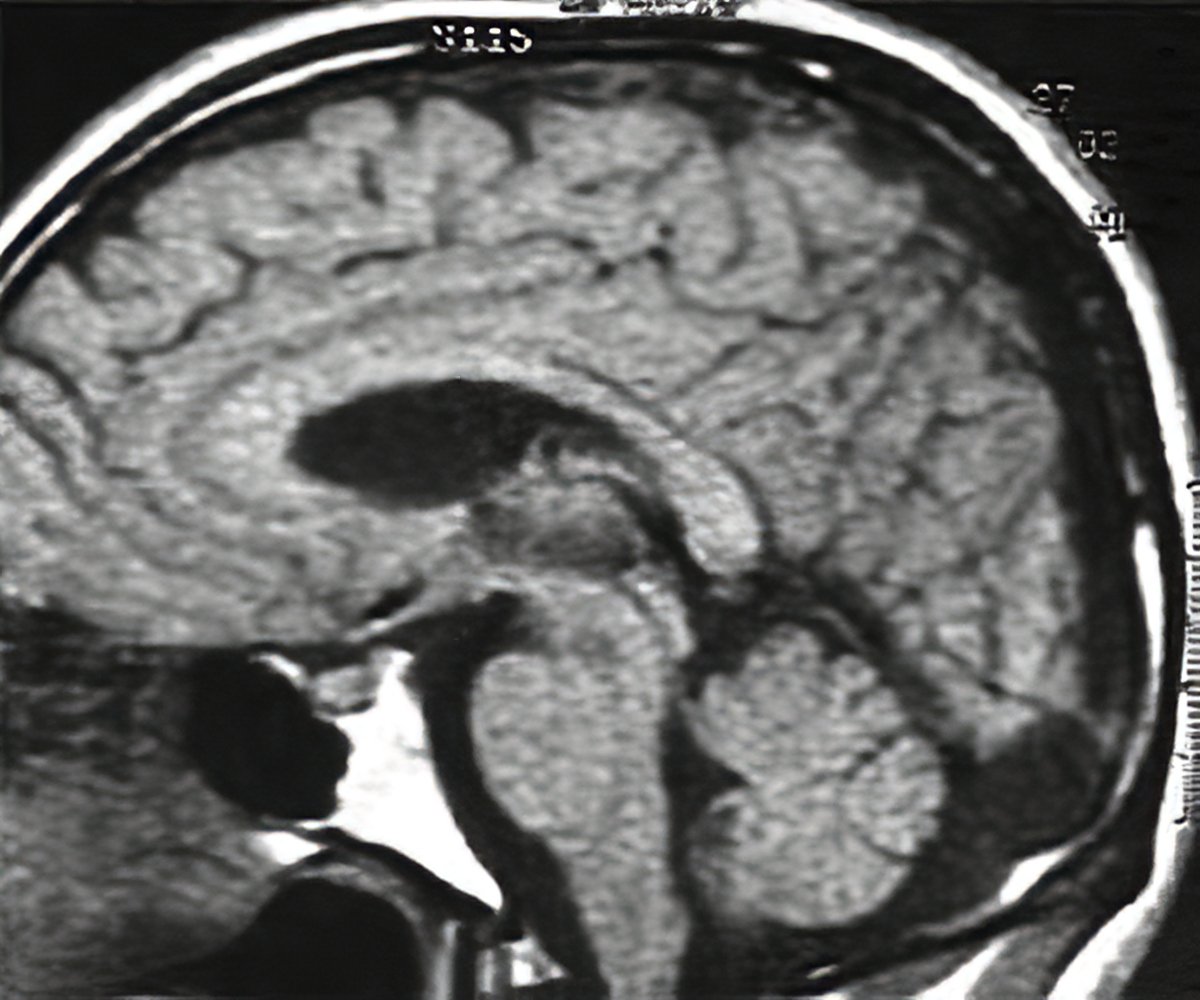

МРТ снимки мальформации Денди-Уокера